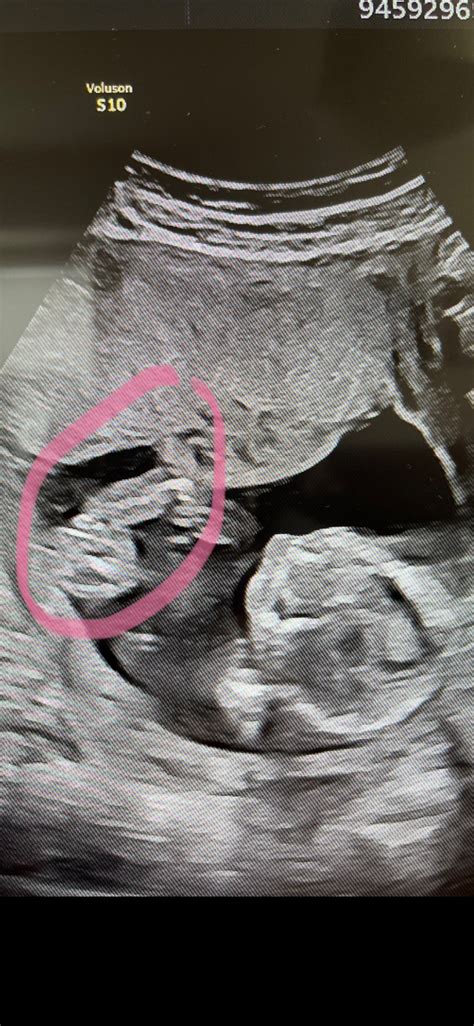

Embryotransfer je jednoduchý, bezbolestný zákrok podobný gynekologickému vyšetreniu. Trvá zvyčajne len niekoľko minút a nevyžaduje anestéziu. Lekár pomocou tenkého katétra zavedie embryo cez krčok maternice do maternice pod ultrazvukovou kontrolou.

Najčastejšie sa uskutočňuje na 3. alebo 5. deň po oplodnení vajíčka (v štádiu blastocysty). Presný deň sa určuje podľa kvality a vývoja embryí a podľa odporúčania embryológa a lekára. Štandardne sa vkladá jedno embryo, aby sa znížilo riziko viacnásobného tehotenstva. V niektorých prípadoch (napr. u starších pacientiek) sa môžu prenášať dve embryá.

Embryo by sa malo uhniezdiť v sliznici maternice. Približne 10 až 12 dní po embryotransfere sa vykonáva tehotenský test z krvi na zistenie hladiny hCG.